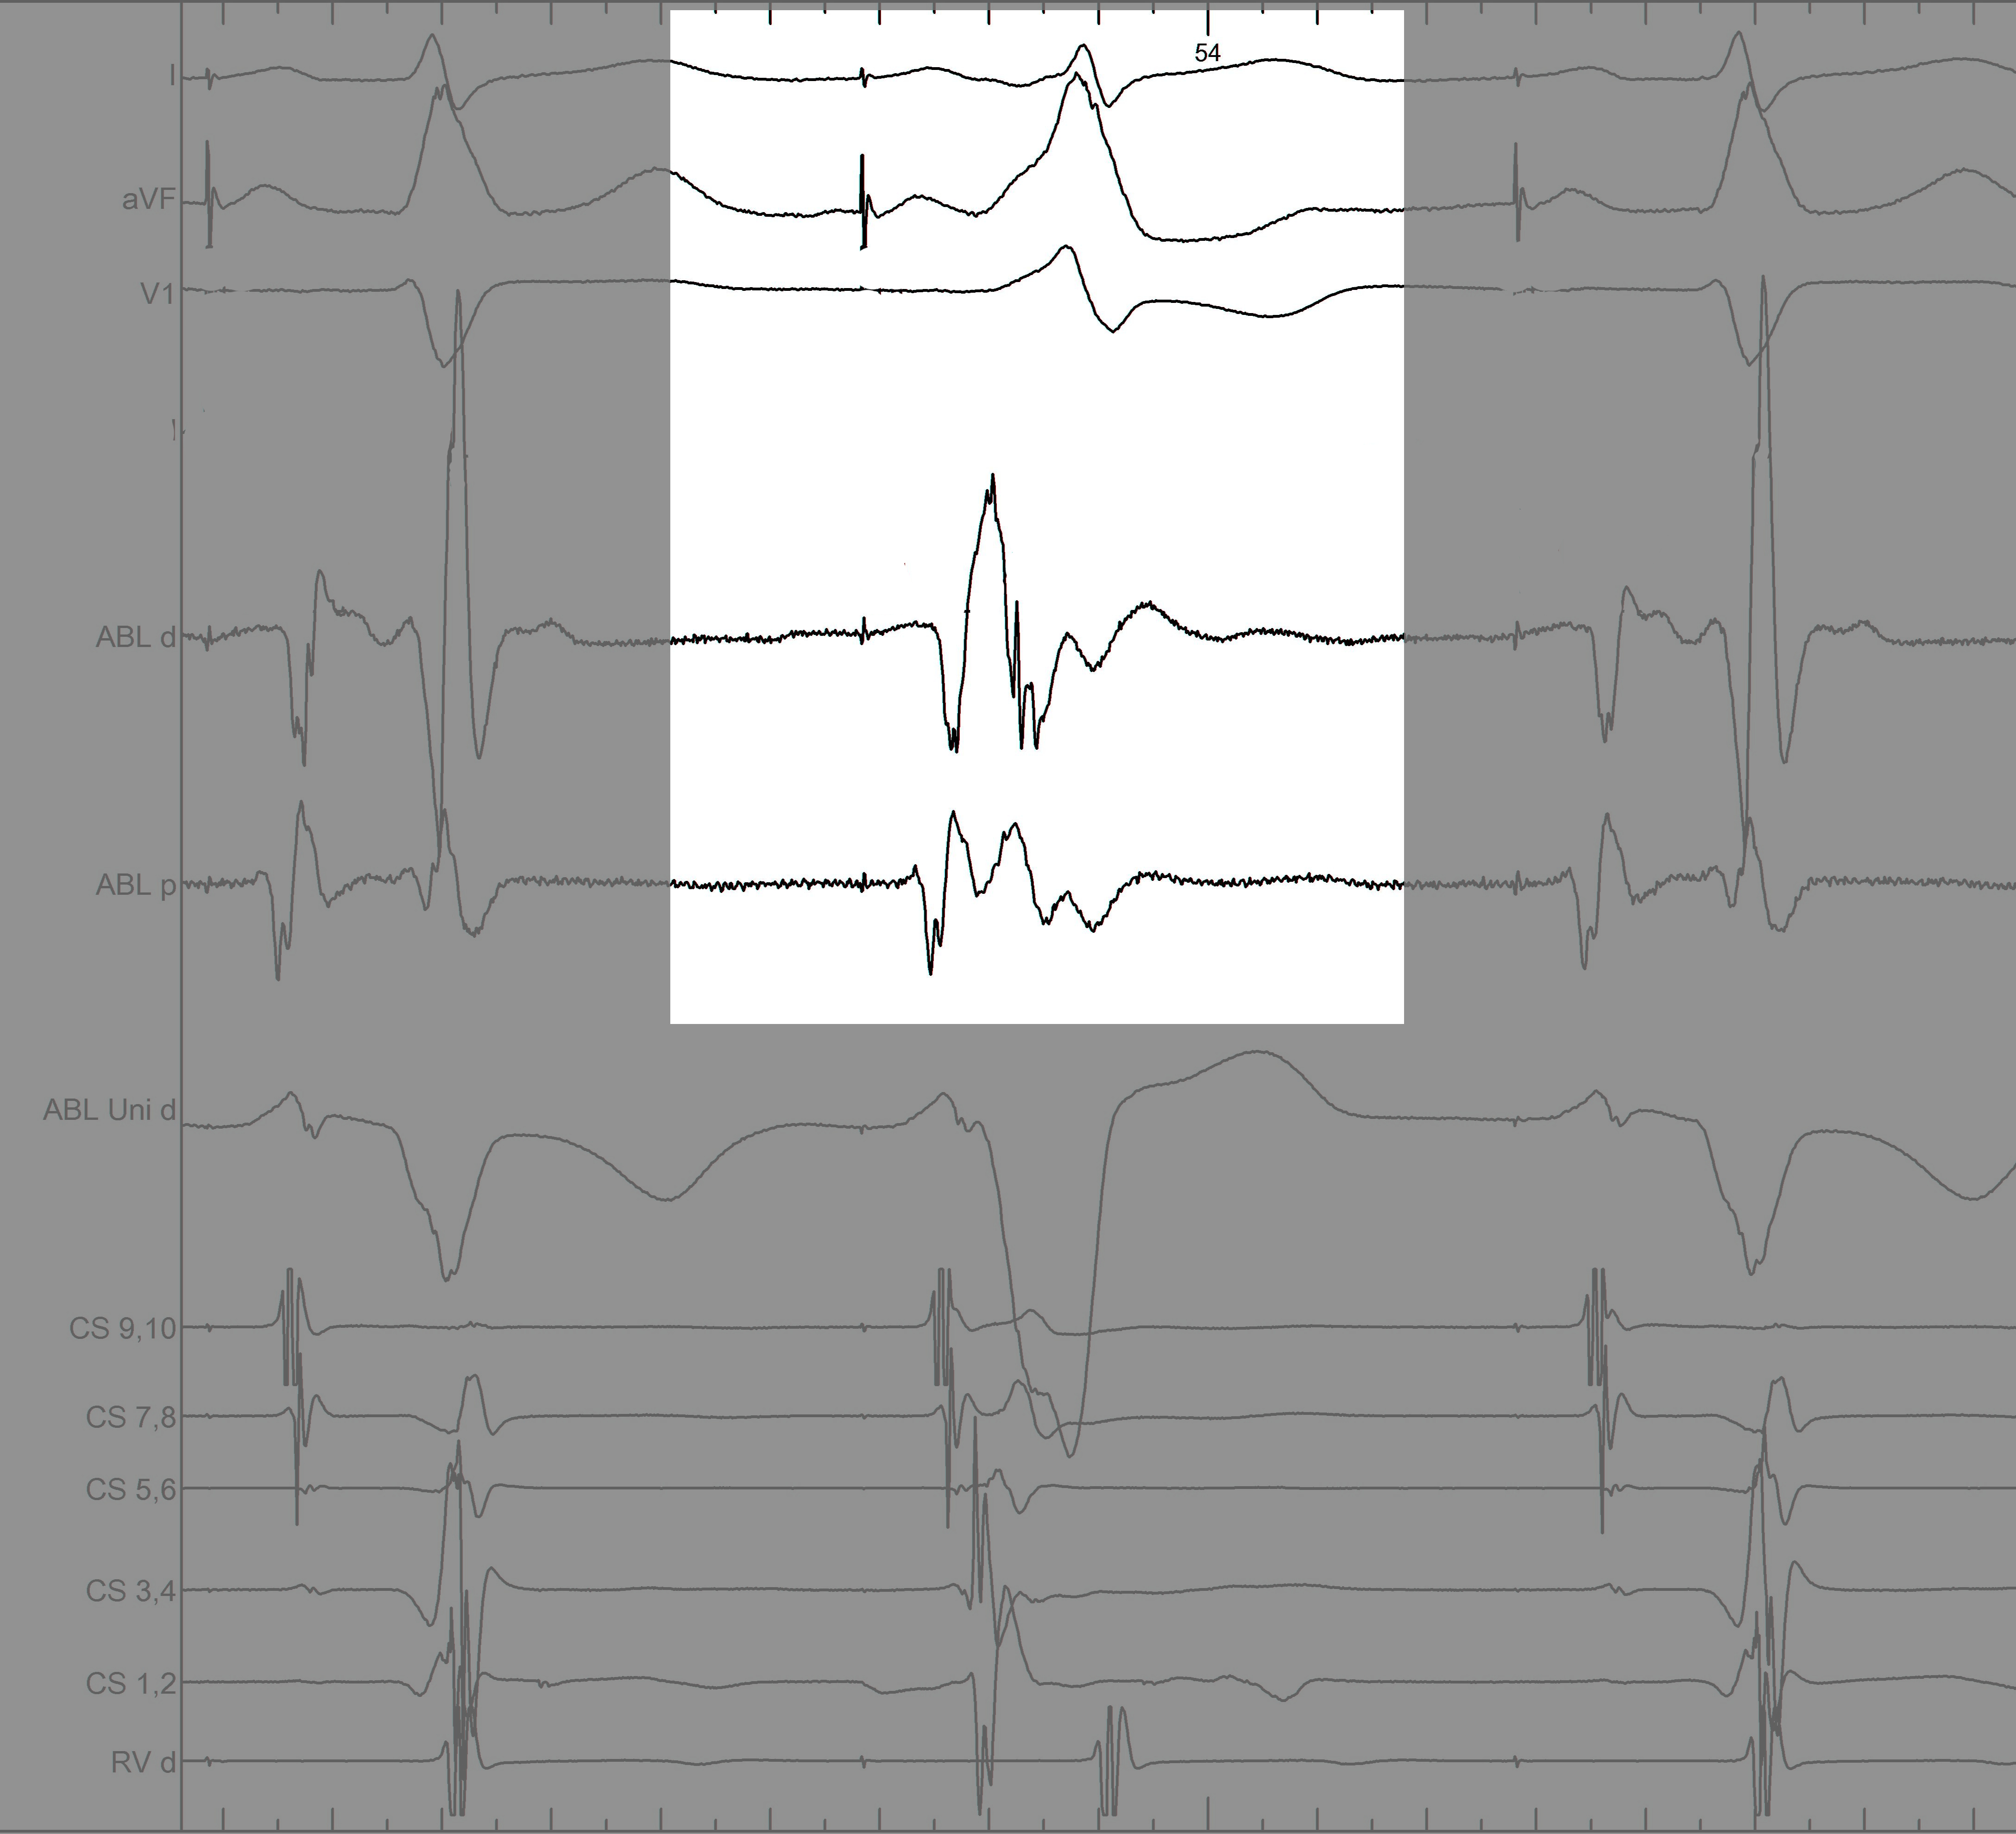

mask1.jpg

Information from other electrodes

mask2.jpg

Unipolar

mask3.jpg

Non preexcited beats

mask4.jpg